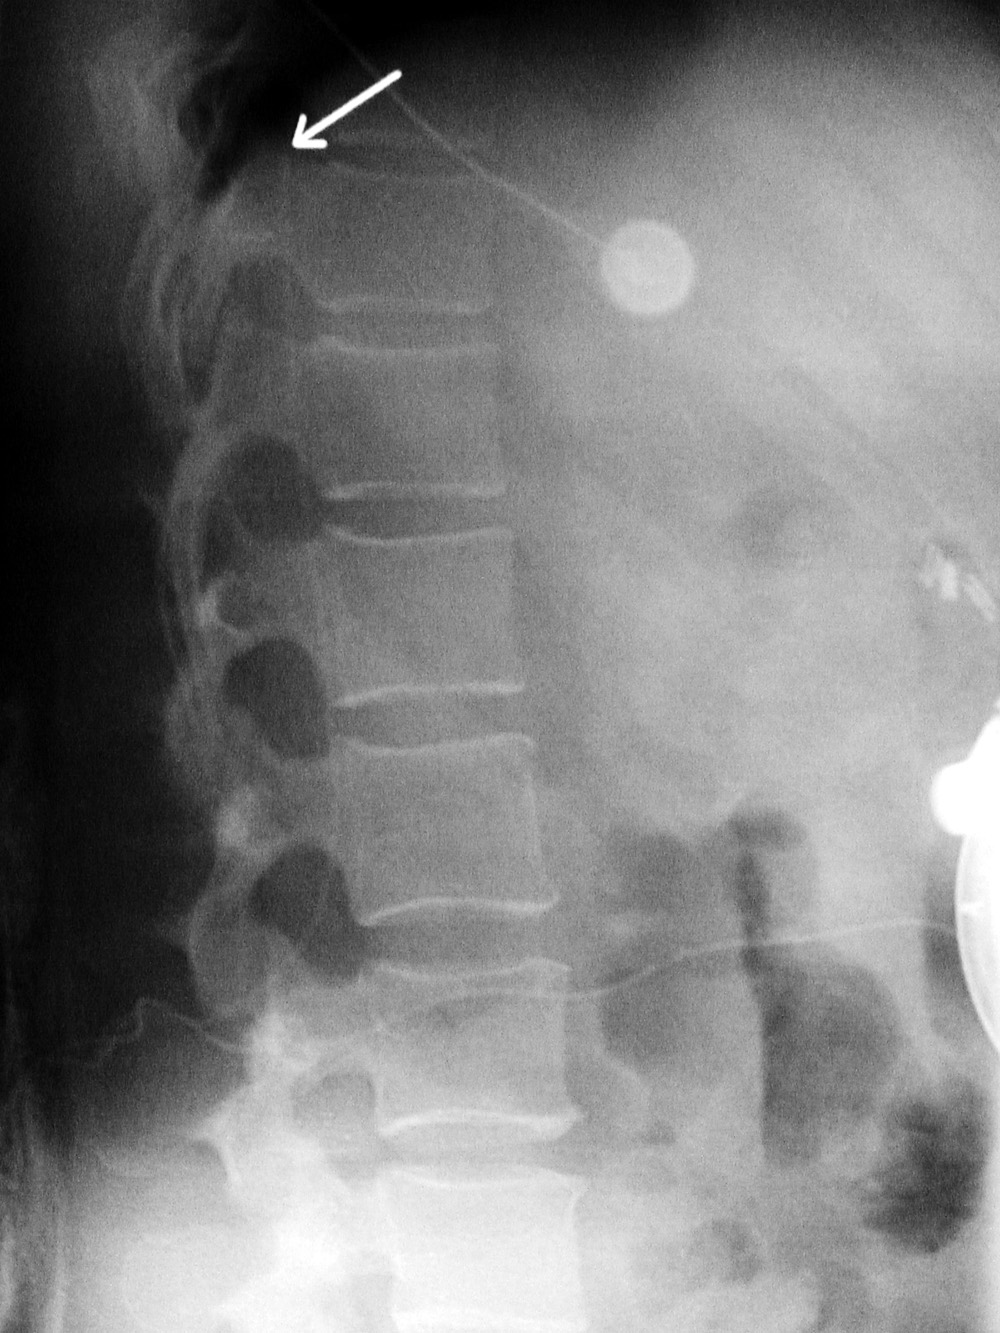

Baclofen intrathecal pump lateral view |

| The catheter (arrow) goes into the lower thoracic spinal subarachnoid space. |

The catheter (arrow) goes into the lower thoracic spinal subarachnoid space. |